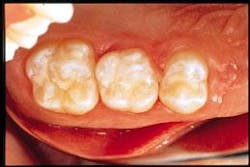

• Light-cure each tooth for 40 seconds (Figure 6). Check for smoothness with a probe or explorer. Note: Surface may be sticky because of an air-inhibited layer. Use ethanol to remove this film.

• Remove rubber dam (Figure 7) and check occlusion, adjusting with a 30-fluted carbide bur or fine diamond followed with either a composite or polishing paste applied with a prophy cup.